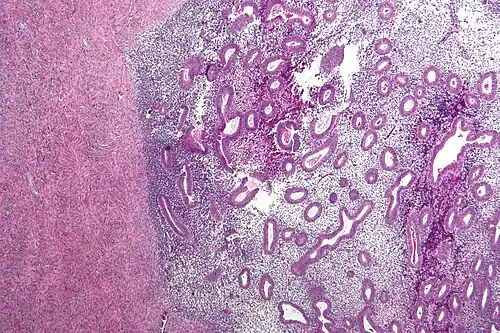

The lesions of superficial endometriosis often appear dark blue or black. In the earlier stages of disease, they may be white, red or yellow-brown. Ovarian cysts are typically dark brown. Adhesions are made up of fibrous scar tissue. Deep endometriosis looks like multiple distinct nodules.[8]

-

Endometriosis, abdominal wall -

Micrograph showing endometriosis (right) and ovarian stroma (left) -